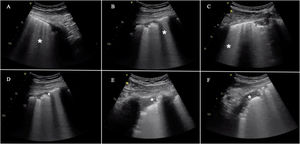

En general, los principales hallazgos ecográficos no difieren de aquellos que podemos observar en pacientes con SDRA de otra etiología y en otras patologías pulmonares, por lo que el hallazgo principal serán las líneasB, reflejando la afectación intersticial o alveolo-intersticial en la neumonía por SARS-CoV-2. No obstante, existen algunas particularidades10,11, como un artefacto característico que aparece en fases precoces (light beam), hiperecogénico, en forma de banda, que se extiende desde una línea pleural regular y un fondo de líneasA, y que aparece y desaparece con el deslizamiento pleural. El resto de los hallazgos se resumen en la figura 3.

Hallazgos frecuentes en pacientes con insuficiencia respiratoria aguda asociada a COVID-19. Incluye la presencia de líneasB en todas sus formas posibles, separadas o coalescentes, llegando incluso a formar una imagen de «pulmón blanco». Pueden partir de la línea pleural o de pequeñas consolidaciones periféricas. A)LíneasB separadas. B)LíneasB coalescentes. C)«Pulmón blanco». D)Línea pleural irregular y fragmentada. E y F)Consolidaciones subpleurales.

Aunque ninguno de estos signos es específico de la neumonía COVID-19, la distribución de estas alteraciones, en un entorno epidemiológico concreto, le otorga una gran especificidad. Es característica la afectación bilateral, en forma de grupos parcheados de líneasB que conviven con otras zonas pulmonares «libres»10,12. Las lesiones tienen una distribución periférica y predominan en campos posteroinferiores, extendiéndose a regiones laterales y anteriores a medida que progresa la enfermedad. Por el contrario, la aparición de derrames pleurales significativos o de grandes consolidaciones lobares obliga a tener en cuenta diagnósticos alternativos o complicaciones12.